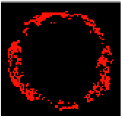

Figure 7 depicts the effectiveness of the KMPSO-mED model by segmenting the overlapping tissues in VH-IVUS images.

Figure 7.

Segmentation by KMPSO-mED: (a) overlapped tissue, and (b) segmented area.